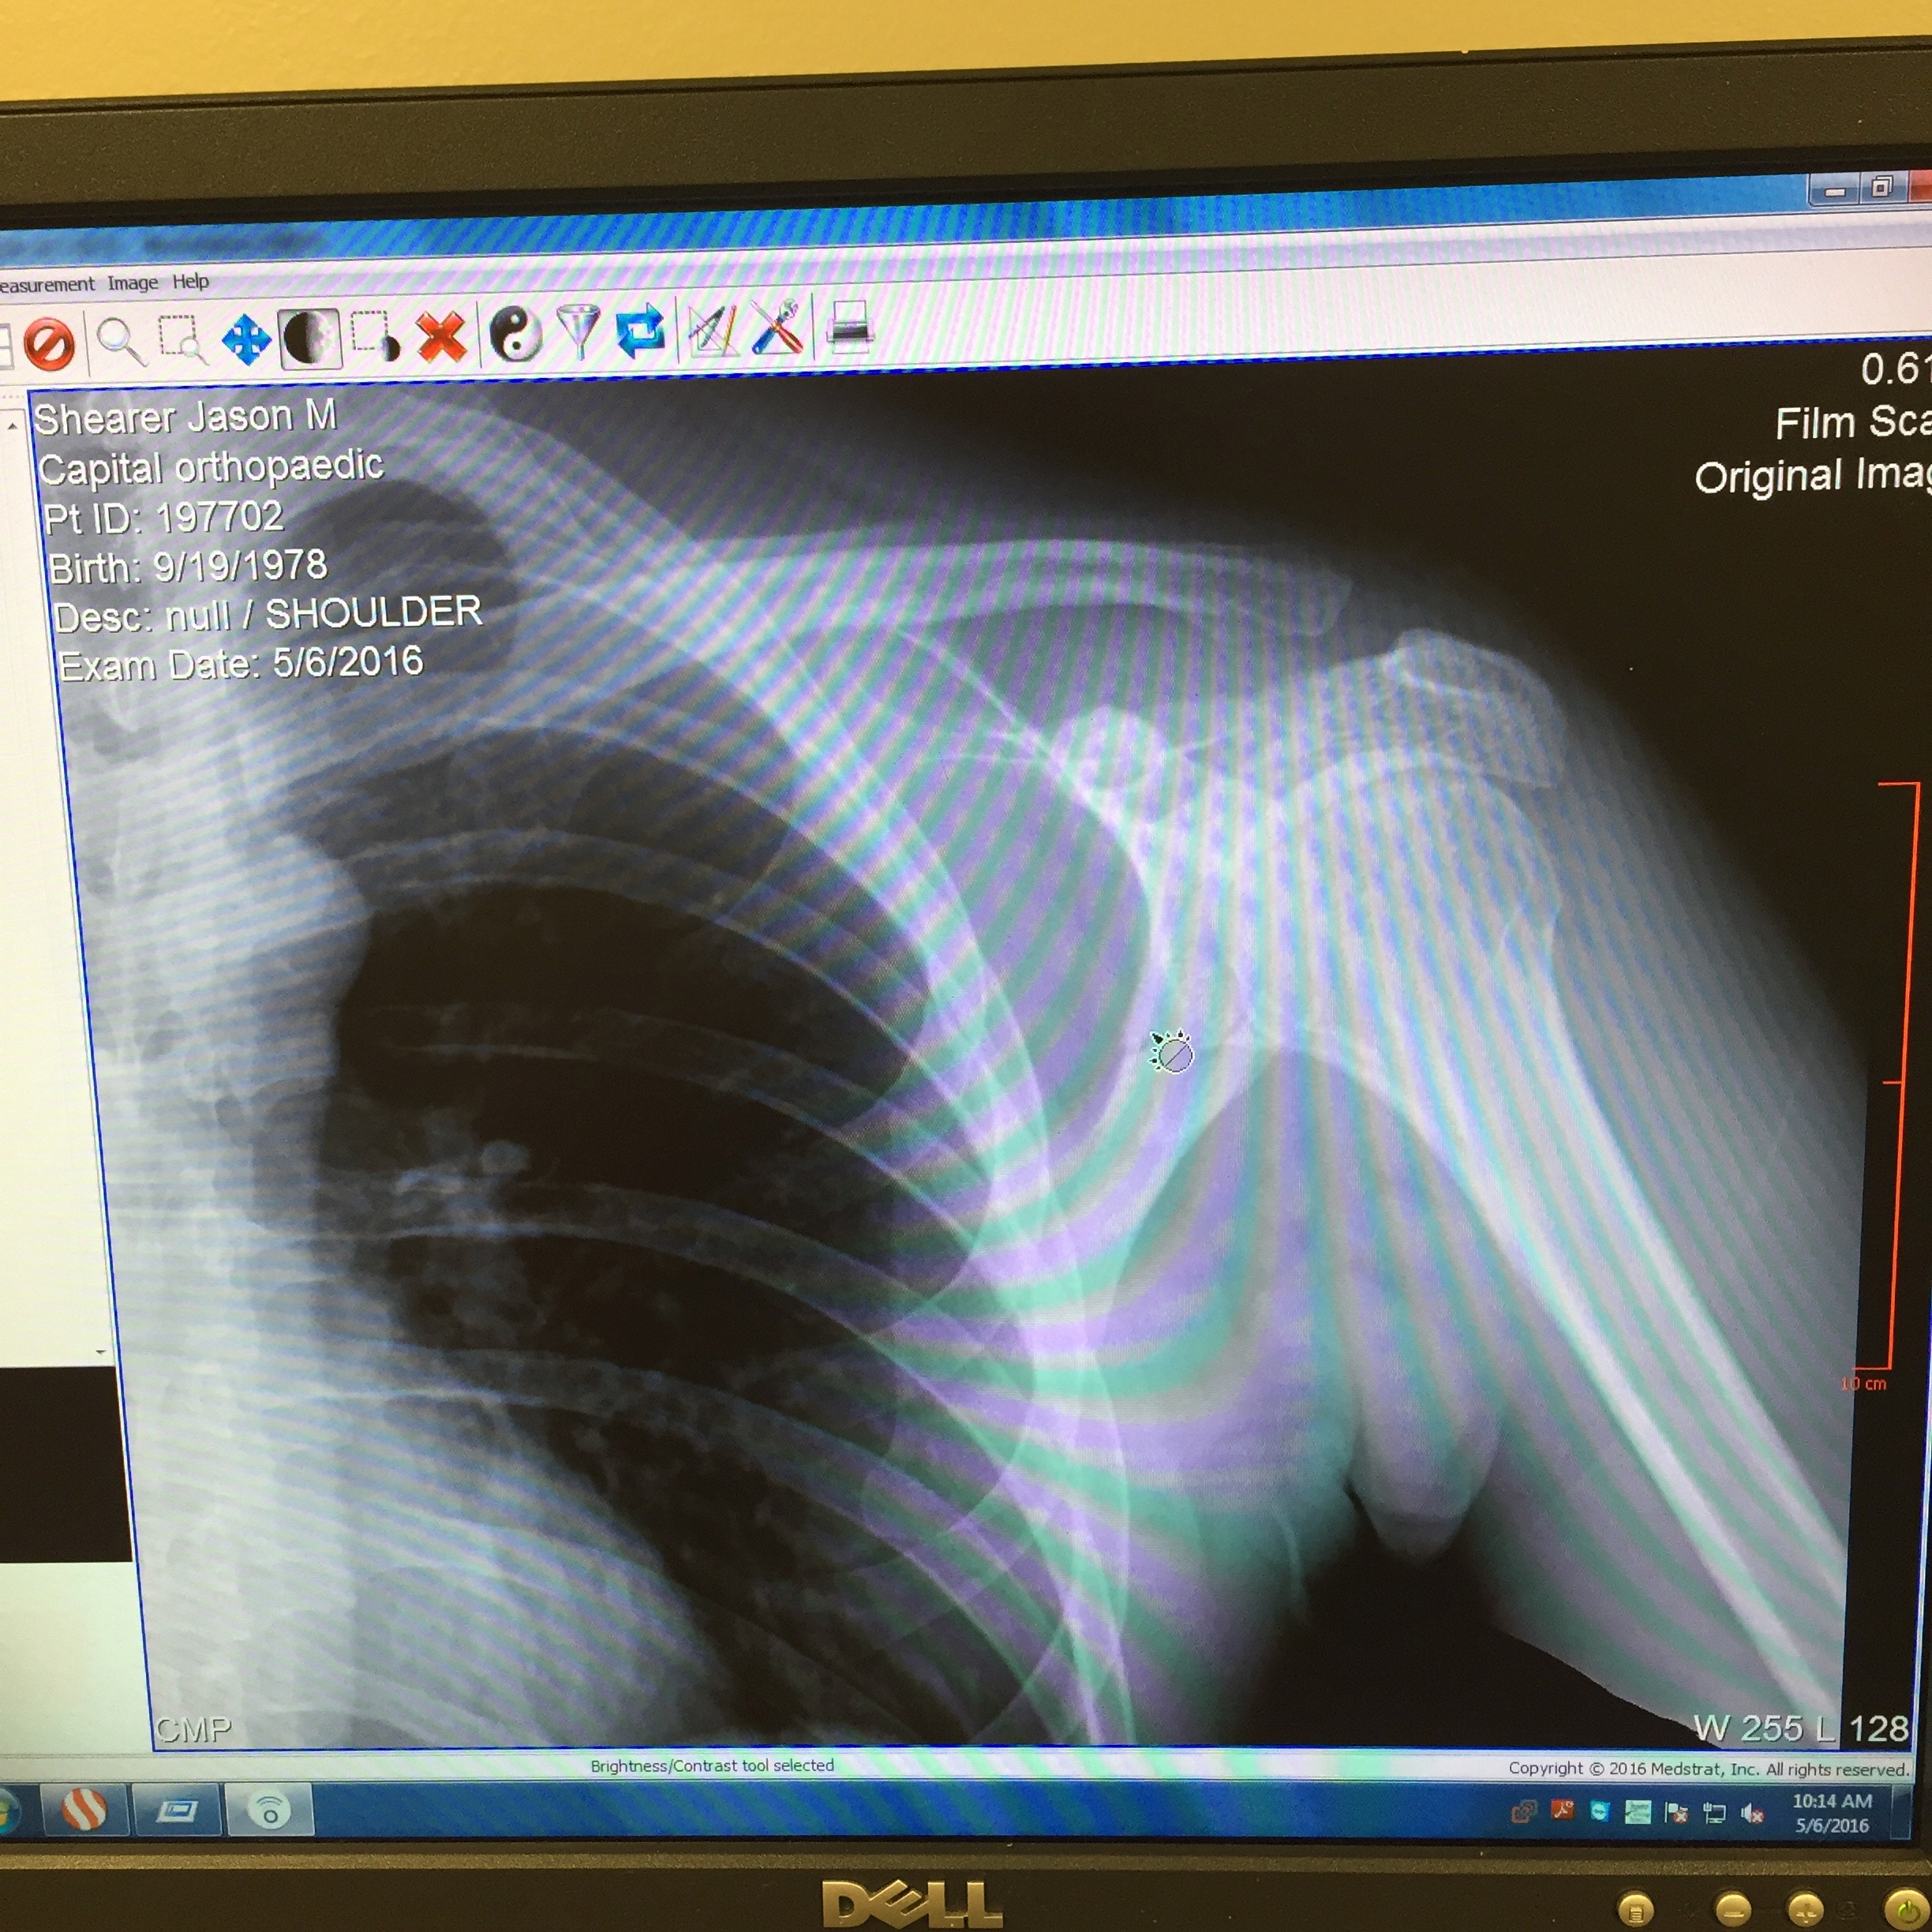

2016 had its highs and lows. If you read my recap of Stagecoach 400 you will know that I was riding a big wave into preparations for Dirty Kanza. That all came to a screeching halt when I was struck by a truck while out on an early AM training ride in May. Broken scapula and a grade 2 separation wasn't going to leave enough time to heal and get back on the horse for a Kanza start.